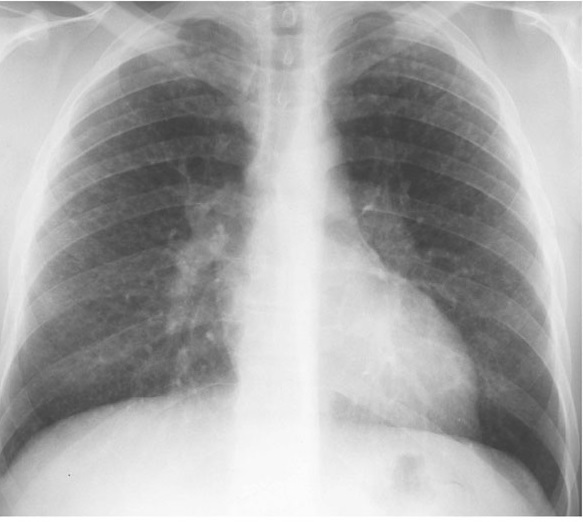

Image radiologique PA d'une pleurésie

purulente chronique du poumon droit . Aspect

radiologique est de plaque fibrosant et

calcification de la plevre du poumon droit .

L'espace intercostale droit est pince , la volume du

poumon droit est diminue et restrictive |

|